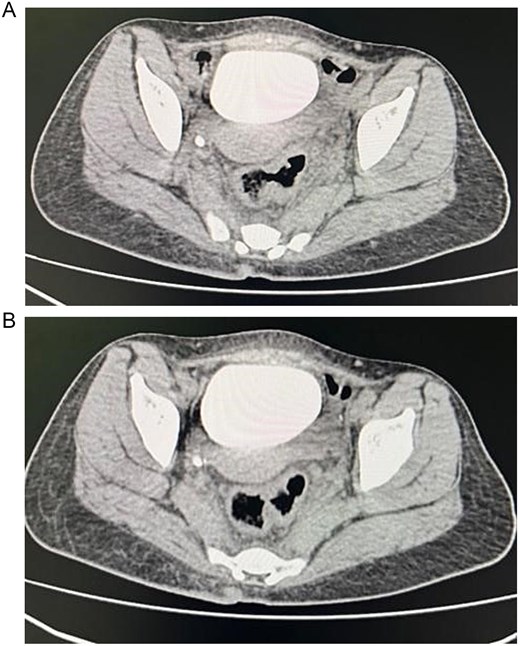

Colonoscopy showed severe luminal narrowing between the junction of the sigmoid and descending colon. Diagnostic cystoscopy confirmed the presence of a fistula opening and demonstrated a villous-like reaction in the urinary bladder mucosa, consistent with a fistulous connection. The fistula opening was located low, raising the possibility of vesicovaginal fistula. Magnetic resonance imaging (MRI) of the abdomen conformed sigmoid diverticulitis and fistula tract to urinary bladder and also possibly a fistula tract extending to the mid-rectum (Fig. 2).